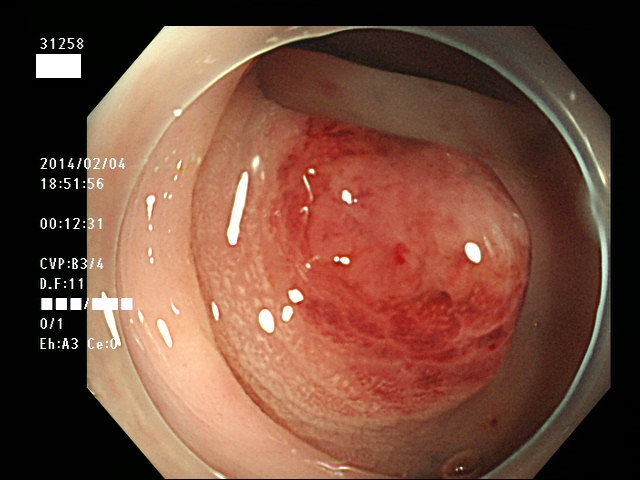

下記の写真は「癌化した過誤腫性ポリープ」です。

![]()